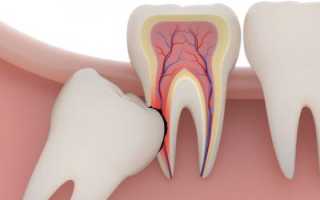

Дистопированный зуб. Занимает неправильное положение и растёт криво или под углом. Он может принимать различное положение: смещаться по оси, упираться в соседний зуб, расти в щеку.

Возможные последствия – неправильный прикус, практическое неучастие в процессе пережёвывания пищи, травмы щеки, языка, воспалённая десна.

- Ретинированный зуб. Прорезывается частично или полностью остаётся в кости, не выходя наружу. Даже если пациента с ретинированной восьмёркой ничего не беспокоит, велик риск возникновения всевозможных инфекций в будущем, постоянного воспаления десны, появления кариеса, пародонтоза и т.д.

- Разрушение, травмирование зуба. Не имея достаточного пространства в зубном ряду, восьмёрка при прорезывании может сильно давить на вторые моляры, приводя к смещению, деформации и механическим повреждениям эмали.

Справка. Зуб мудрости зачастую дистопируется по причине позднего прорезывания, – места для правильного расположения зубов в челюсти не хватает, да и зубов, оказывающих поддержку и задающих вектор роста, попросту нет, поэтому частенько они растут с наклоном, мешая вторым молярам.